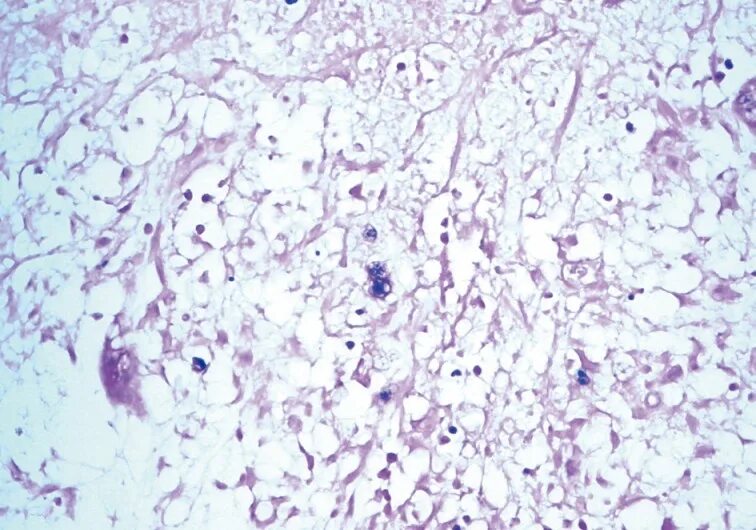

Окрашивание гистологического препарата